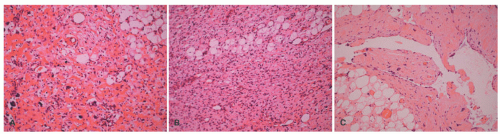

FIGURE 24-9. Myxoid-reticular pattern in schwannoma. Microcystic/reticular schwannoma. Views from three representative cases, highlighting the characteristically microcystic or reticular growth patterns. Obtained with permission Liegl B, Bennett MW, Fletcher CD. Microcystic/reticular schwannoma: a distinct variant with predilection for visceral locations. Am J Surg Pathol. 2008;32(7):1080-1087.

FIGURE 24-14. Granular cell tumor. Note the presence of pseudoepitheliomatous changes in the surface epidermis (A-C). Such changes can be confused with those of squamous cell carcinoma. Nested and diffuse sheets of uniform, pale rounded to ovoid to spindle shaped with abundant eosinophilic granular cytoplasm are the principal microscopic features of this tumor (D-F). Obtained with permission Dehner LP, Gru AA. Nonepithelial tumors and tumor-like lesions of the skin and subcutis in children. Pediatr Dev Pathol. 2018;21(2):150-207.

FIGURE 24-15. A-C, Granular cell tumor presenting in the skin on the shoulder of a 9-year-old female. A, The dermis at this magnification is seemingly unremarkable, which may be the initial impression in a granular cell tumor with a diffuse infiltrative pattern. B, Granular cells are infiltrating into superficial subcutaneous fat. C, S-100 protein immunostain demonstrates the striking number of granular cells in the dermis.